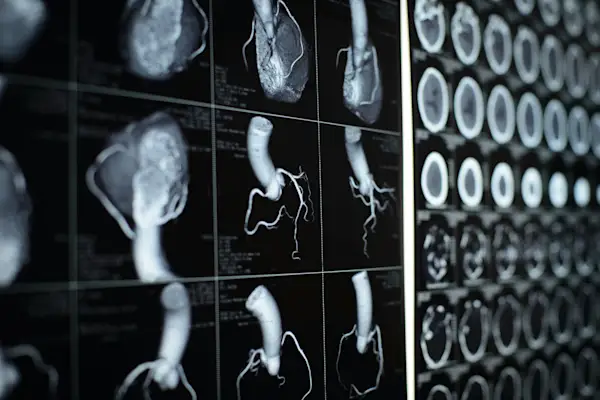

CT扫描心

7种诊断心脏瓣膜病的方法

了解您的心脏瓣膜手术选择